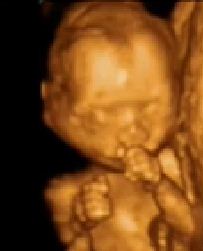

21 Haftalik Gebelik Hamilelik Ultrason Goruntuleri

20 Haftalik Gebelik Bebek Goruntusu 4 Boyutlu Kilosu Gelisimi Hareketleri